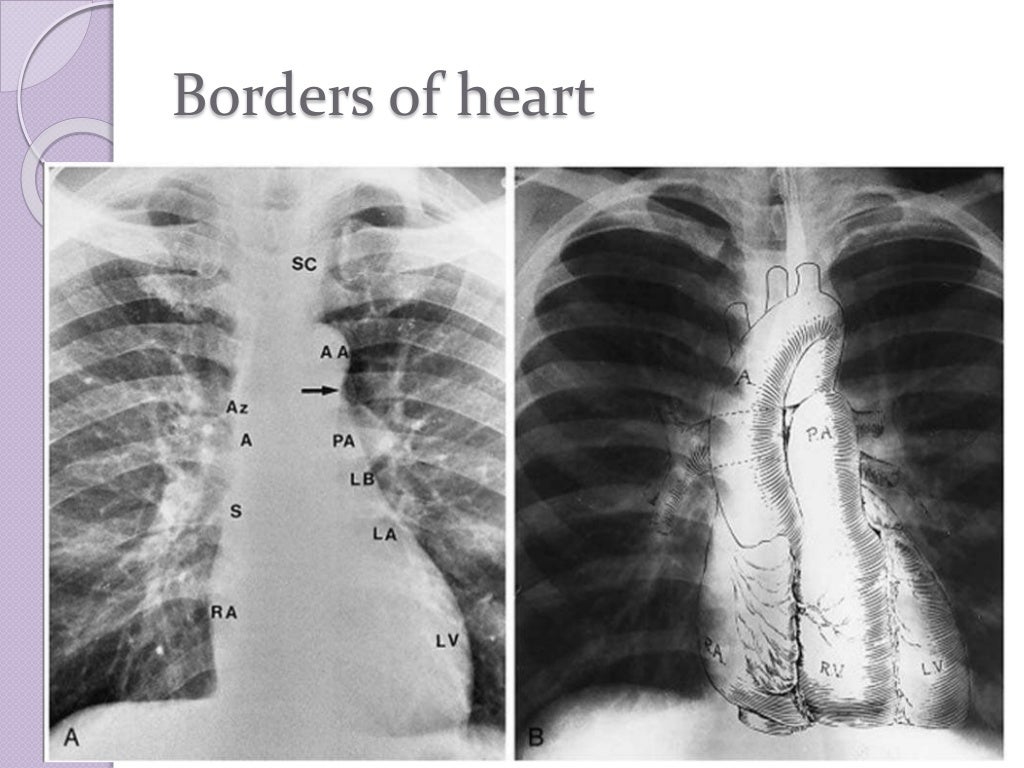

Diagnostic radiology of cardiovascular 2009 Diagnostic Radiology Chest And Cardiovascular Imaging radiography allows visualization and assessment of the chest wall, mediastinum, and hila including the heart and great vessels, central airways,. cardiovascular imaging is a branch of diagnostic radiology where a cardiac radiologist oversees or performs medical. this new edition is a complete guide to diagnostic imaging of the chest and cardiovascular system. Diagnostic Radiology Chest And Cardiovascular Imaging.

Diagnostic radiology of cardiovascular 2009 Diagnostic Radiology Chest And Cardiovascular Imaging radiography allows visualization and assessment of the chest wall, mediastinum, and hila including the heart and great vessels, central airways,. this new edition is a complete guide to diagnostic imaging of the chest and cardiovascular system. cardiovascular imaging is a branch of diagnostic radiology where a cardiac radiologist oversees or performs medical. Diagnostic Radiology Chest And Cardiovascular Imaging.